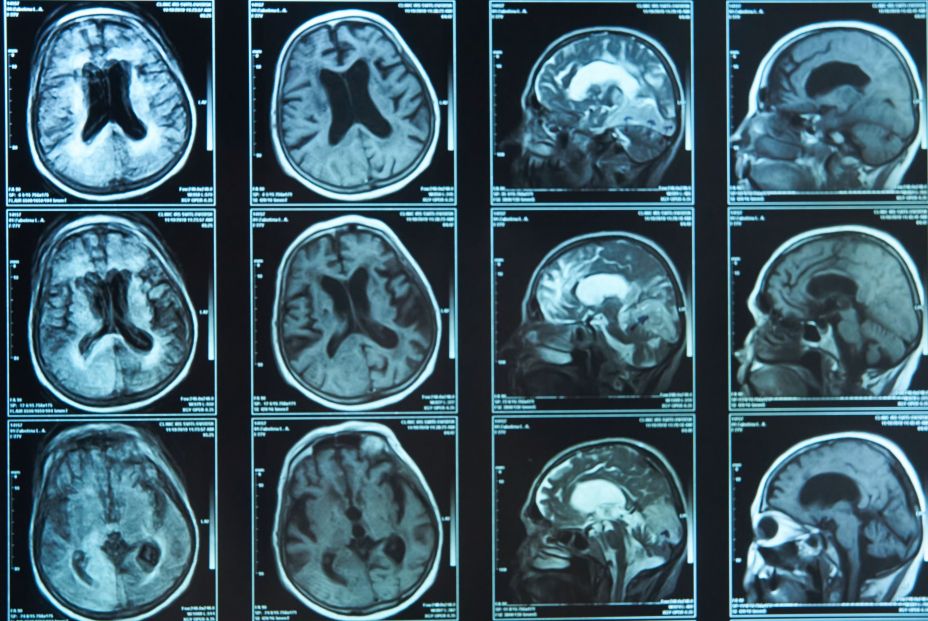

Para obtener un diagnóstico acertado, los especialistas emplean, entre otras cosas, la tomografía por emisión de positrones (o PET). "La PET es una técnica de imagen médica utilizada ampliamente en oncología y neurología que permite obtener una imagen tridimensional de la distribución de una molécula objetivo", explica el doctor Silva-Rodríguez.

En el caso de la técnica FDG-PET empleada en el estudio, la molécula objetivo es un análogo de la glucosa conocido como FDG. Afirma el doctor que "existe una fuerte evidencia de que la disminución del consumo de glucosa y, por ende, de la captación de FDG-PET, permite 'fotografiar' in vivo el proceso de neurodegeneración. Cada patología neurodegenerativa (enfermedad de Alzheimer, demencia con cuerpos de Lewy, demencia frontotemporal, etcétera) produce degeneración en áreas distintas del cerebro, un patrón único de cada enfermedad". Aunque hoy en día la imagen FDG-PET está indicada para el diagnóstico temprano de la gran mayoría de las enfermedades neurodegenerativas, existen muy pocas evidencias de que estos patrones de neurodegeneración puedan aparecer incluso sin síntomas clínicos de la enfermedad.

"El principal hallazgo de nuestro trabajo es que la técnica de imagen FDG-PET permite identificar individualmente a pacientes con una patología subyacente de cuerpos de Lewy, incluso aunque estos no hayan desarrollado ningún síntoma clínico de la misma. En nuestro trabajo observamos que un porcentaje considerable de pacientes con un diagnóstico clínico de Alzheimer tienen hallazgos en la FDG-PET más similares a los observados en pacientes con demencia de cuerpos de Lewy, y hemos demostrado que estos pacientes realmente tienen menos patología de alzhéimer y -gracias a un seguimiento de hasta 6 años- que desarrollarán síntomas clínicos típicos de la demencia de cuerpos de Lewy en el futuro", señala el experto en neuroimagen dentro del grupo de investigación, el Doctor Michel Grothe.